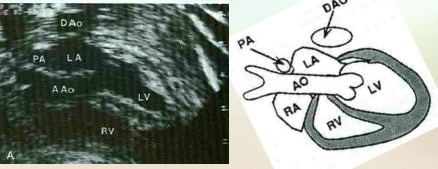

what is speciat about these veiws of the <3 ?

Left Ventricular Outflow Tract – AKA Aortic root or 5-Chamber view

Right Ventricular Outflow Tract

what does the left ventricular outflow tract (LVOT) demonstrate?

continuity of the interventricular septum to the aortic root

what does the rt ventricular outflow tract (RVOT) demonstrate?

Demonstrates main pulmonary artery